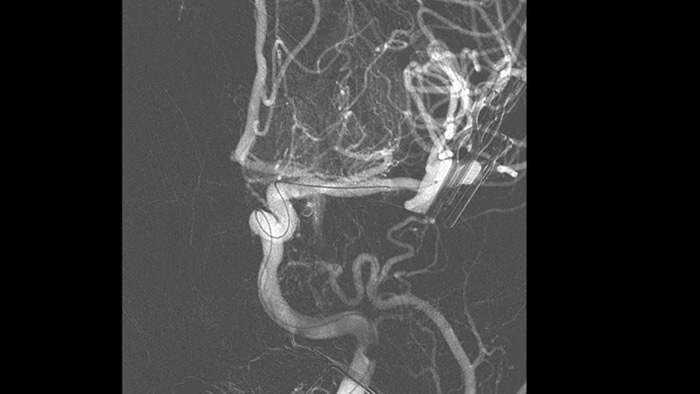

Melhorar a visualização do sistema vascular

Roadmap Pro

Tome decisões informadas sobre se o coágulo pode ser alcançado e qual o percurso a ser usado. O Roadmap Pro, um mapa avançado de duplo contraste, ajuda a melhorar a visualização de vasos sobrepostos, ao mesmo tempo que equilibra a exposição à radiação.

Visualização de DSA

As visualizações de DSA de alta qualidade permitem avaliar se a recuperação completa do coágulo foi alcançada e se partes de coágulo foram dispersas distalmente no cérebro. Pode verificar a restauração do fluxo sanguíneo para a penumbra e verificar se existe hemorragia peri-procedimento.